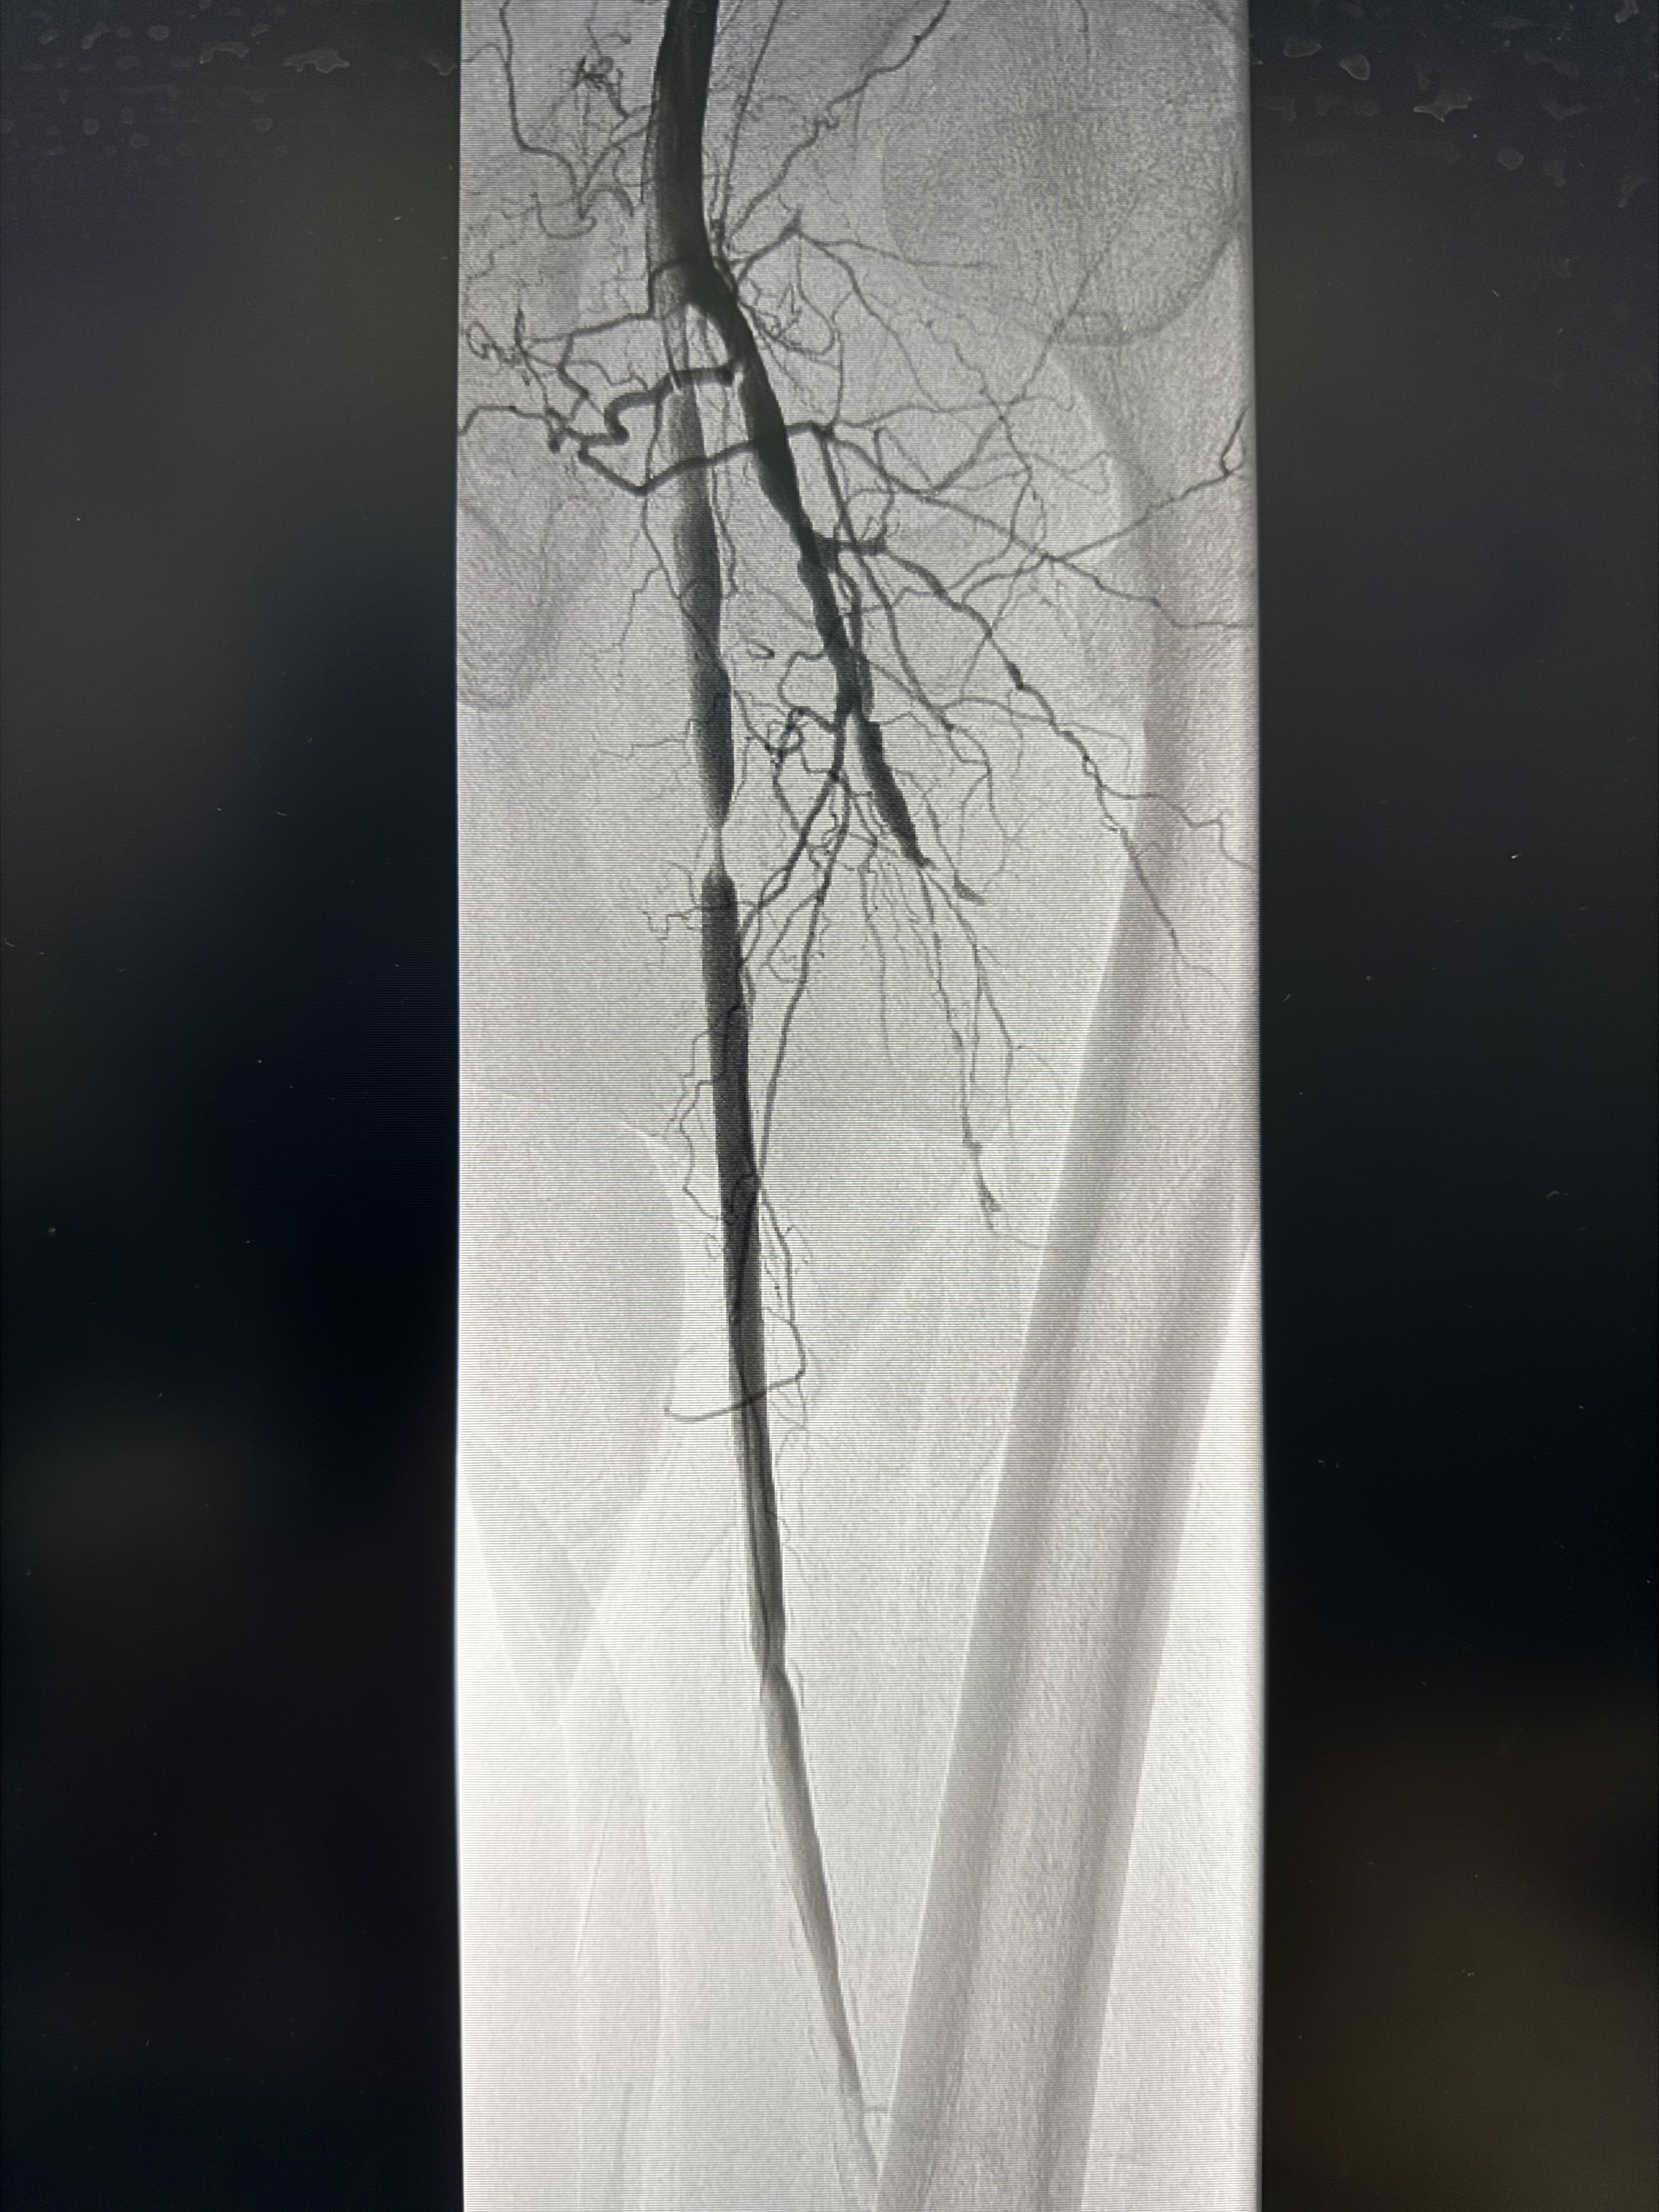

手術(shù)案例分享2——下肢動脈硬化閉塞癥

患者術(shù)前造影股淺上段狹窄伴局段閉塞,膕動脈多發(fā)狹窄伴局段閉塞。膕動脈病變放大特寫膝下流出道差,僅脛前動脈部分顯影術(shù)中予以hawk減容膝下球囊擴張,可見明顯充盈缺損(病變重度鈣化所致)術(shù)后管腔獲得滿意,膝下流出道脛前腓動脈流速好hawk切出的斑塊